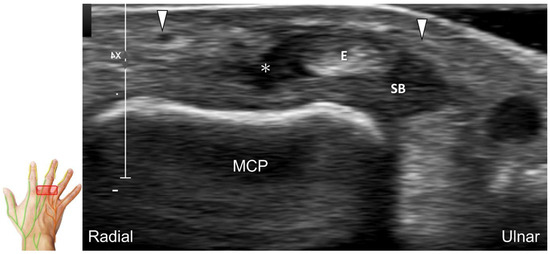

Scanning Technique

The transducer is positioned on the axial plane of the dorsal metacarpal joint in the target digit. The dorsal proper digital nerves can be found on either side of the sagittal band (Figure 33A). The transducer is moved proximally and the dorsal common digital nerves can be observed superficial to the extensor (usually the extensor digitorum proprius) tendons (Figure 33B). By returning to the level of the sagittal band and moving the transducer distally, the dorsal proper digital nerves can be seen superficial to and alongside the central slip of the finger extensor tendon (Figure 33C). Alternatively, moving the transducer distally toward the proximal phalanx of the first to the radial aspect of the fourth phalanx allows observation of the nerve fascicles of the palmar proper digital nerve originating from the median nerve (Figure 33D).

Figure 33. Sonographic imaging of the dorsal common digital nerve on the metacarpal bone (A), toward the metacarpal head (B). Dorsal proper digital nerves on the proximal phalanx (C), and the terminal nerve originating from the palmar proper digital nerve on the distal phalanx of third finger (D). Arrowheads: dorsal common digital nerve; arrows: palmar proper digital nerve. MCP: metacarpal bone; SB: sagittal band; E: extensor tendon; Cs: central slip; PP: proximal phalanx; T: terminal band; DP: distal phalanx; DIO, dorsal interosseous muscle.